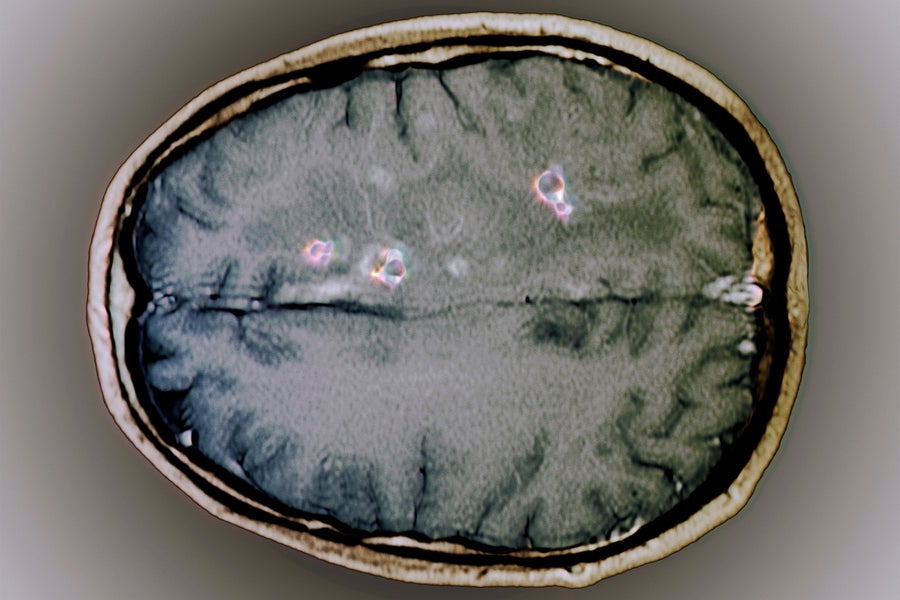

Magnetic resonance imaging (MRI) scan of an axial section through the brain of a 25-year-old patient, showing cysts (purple) from a tapeworm infection. Zephyr/Getty Images

Earlier this week, news broke that independent presidential candidate Robert F. Kennedy, Jr., claimed to have once had a dead worm in his brain. Kennedy had been experiencing memory loss and mental fog, and he originally suspected these symptoms might be caused by a brain tumor. Brain scans in 2010 showed a cyst that his doctors said contained remains of a parasite. The findings and other health issues were revealed in a New York Times article based on a review of a deposition for his 2012 divorce, as well as an interview the outlet conducted with him.

The species of the purported parasite in Kennedy’s brain was never identified, and he did not know where he got infected. A spokesperson told media outlets on Wednesday that Kennedy had traveled extensively to Africa, South America, and Asia and likely contracted the parasite on one of the trips. Several parasites can affect the central nervous system and potentially create cysts in brain tissue. While relatively uncommon in the U.S., such infections can be devastating in many parts of the world. For example, the World Health Organization estimates there are between 2.56 million and 8.3 million people around the globe living with neurocysticercosis, a brain infection caused by the pork tapeworm Taenia solium. “It’s a really big deal in Latin America, sub-Saharan Africa, India, and other parts of Asia. It’s a leading cause of acquired seizures,” says Clinton White, a parasitologist and infectious diseases professor at the University of Texas Medical Branch at Galveston. “Neurocysticercosis is a major disease, and it’s kind of funny [these are] the circumstances in which people are paying attention to it.”